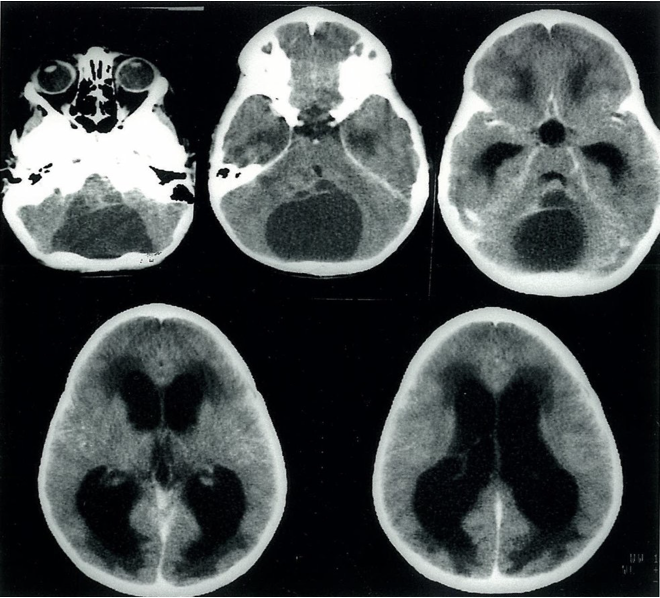

Noncommunicating hydrocephalus Cranial CT (axial view) of a 13-year-old boy

A large, liquor-like, hypodense lesion is located in the posterior cranial fossa in images 1ā3. This lesion is most likely an arachnoid cyst compressing the cerebral aqueduct), which prevents the free circulation of the CSF from the ventricles to the subarachnoid space. As a result, the third ventricle and the lateral ventricles are dilated, and there is transependymal egress of CSF